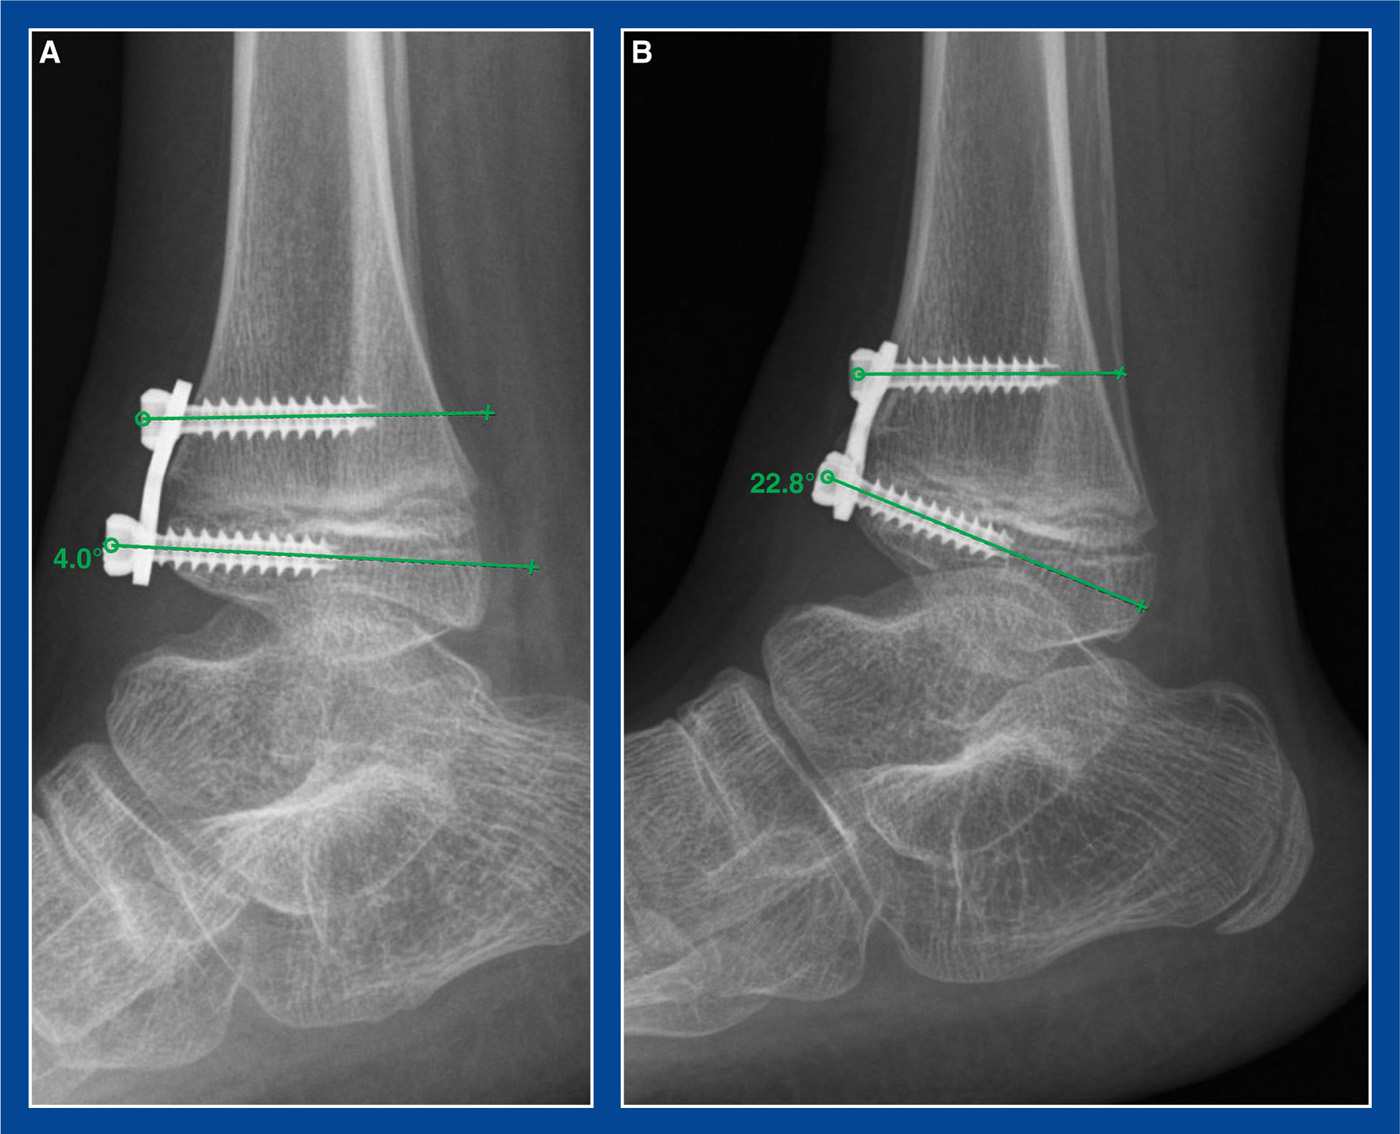

From www.mdpi.com

Medicina Free FullText Syndesmosis Changes before and after Syndesmotic Screw Removal A Screw Removal From Tibia Hello, i broke my tibia in april 2018 and had surgery to insert a plate and 9 screws. The plates screwed to the outside of the tibia were easy to remove. Cover bone and tissue in packs. Here are 10 indications for hardware removal after fracture fixation: Knee problems come when you have alignment problems in. If a tendon is. Screw Removal From Tibia.